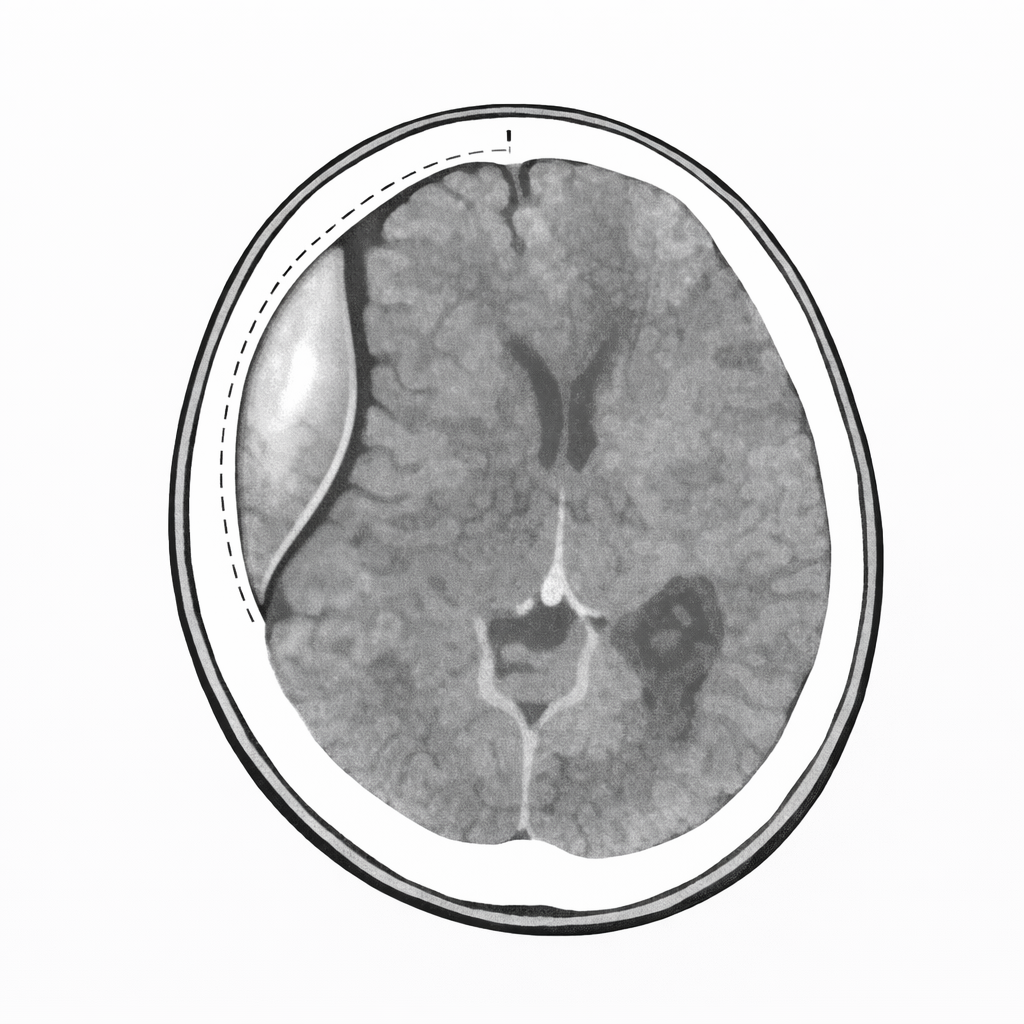

■ 血腫との関係(ここ超重要)

● 硬膜外血腫

出血部位:

頭蓋骨と硬膜の間

硬膜は頭蓋骨に強く張り付いているが、

外傷などで動脈(中硬膜動脈など)が破綻すると

頭蓋骨と硬膜の間に血液が溜まり、

硬膜が内側へ押し剥がされる。

その結果:

CTでは 凸レンズ状(両凸型) に見える。

⸻

● 硬膜下血腫

硬膜とくも膜の間

この間は本来「くっついているが固定は弱い」。

架橋静脈が破綻すると、

血液は比較的広く広がることができる。

CTでは 三日月型(半月状) に見える。

■ 形の違いの本質

硬膜外血腫

→ 硬膜が頭蓋骨にへばりついている

→ 剥がされて内側に膨らむ

→ 両凸型

硬膜下血腫

→ 硬膜とくも膜の間は広がれる

→ さーっと広がる

→ 三日月型

■ 位置関係の最終整理

頭蓋骨

↓

硬膜

くも膜

くも膜下腔(脳脊髄液)

軟膜

脳